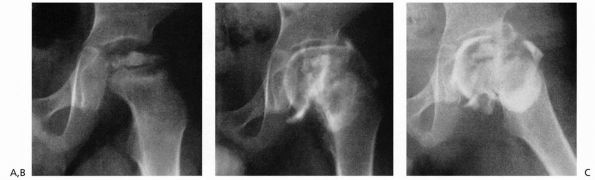

FIGURE 15-23. A 4-year, 9-month-old boy with Catterall group 4 disease and at-risk status. (A) Plain film. (B)

Arthrogram in neutral abduction, adduction, and rotation. Note enlargement and flattening of the cartilaginous femoral head and how the lateral margin of the acetabulum is deformed by the femoral head. (C) Arthrogram in abduction and slight external rotation. Note how the femoral head hinges on the lateral edge of the acetabulum, further deforming the lateral acetabulum. Also note the slight pooling of dye medially. (Weinstein SL. Legg-Calvé-Perthes disease. In: Morrissy RT, Weinstein SL, eds. Lovell and Winter’s Pediatric Orthopaedics, 5th Ed. Philadelphia: Lippincott Williams & Wilkins, 2001:966) |

the head actually can be contained and, if so, in what position this is

best accomplished. Arthrography demonstrates any flattening of the

femoral head that may not be seen on plain film. More important, it may

demonstrate the hinge abduction phenomenon, which is a contraindication

to any type of containment treatment. Once the femoral head becomes

deformed and is no longer containable within the acetabulum, the only

motion that is allowed is in the flexion and extension plane, with

abduction leading to hinging on the lateral edge of the acetabulum.

This hinge abduction causes acetabular and secondary femoral head

deformity (Figure 15-23).